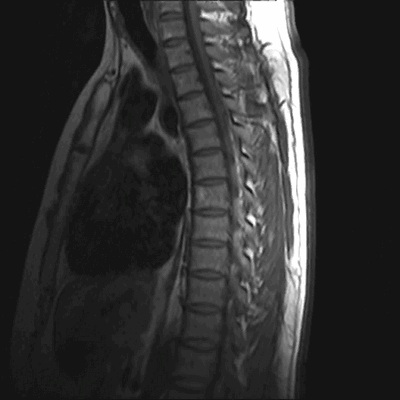

МРТ позвоночного столба: грыжа диска L4-L5 (сагиттальная плоскость, Т2 ВИ)

МРТ позвоночника. Сагиттальная Т2-взвешенная МРТ, срединный срез поясничного отдела. Показана нумерация позвонков, измерения позвоночного канала (черная линия). Т- дуральный мешок с ярким ликвором. L- желтая связка. Sacrum - крестец. D - межпозвоночный диск. Голубым выделен остистый отросток, желтым - тело позвонка, Голубые точки - ход корешков.